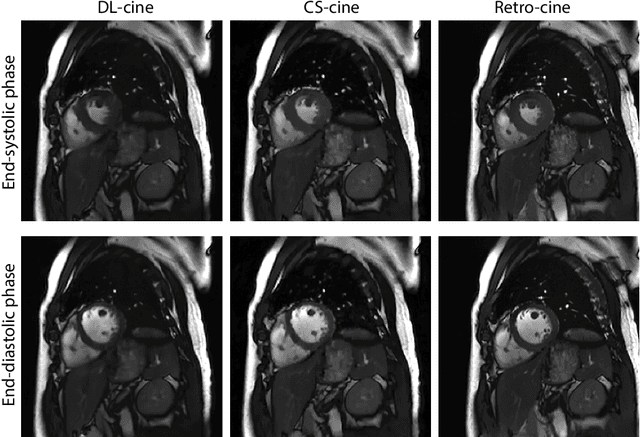

Retrospectively gated cine (retro-cine) MRI is the clinical standard for cardiac functional analysis. Deep learning (DL) based methods have been proposed for the reconstruction of highly undersampled MRI data and show superior image quality and magnitude faster reconstruction time than CS-based methods. Nevertheless, it remains unclear whether DL reconstruction is suitable for cardiac function analysis. To address this question, in this study we evaluate and compare the cardiac functional values (EDV, ESV and EF for LV and RV, respectively) obtained from highly accelerated MRI acquisition using DL based reconstruction algorithm (DL-cine) with values from CS-cine and conventional retro-cine. To the best of our knowledge, this is the first work to evaluate the cine MRI with deep learning reconstruction for cardiac function analysis and compare it with other conventional methods. The cardiac functional values obtained from cine MRI with deep learning reconstruction are consistent with values from clinical standard retro-cine MRI.